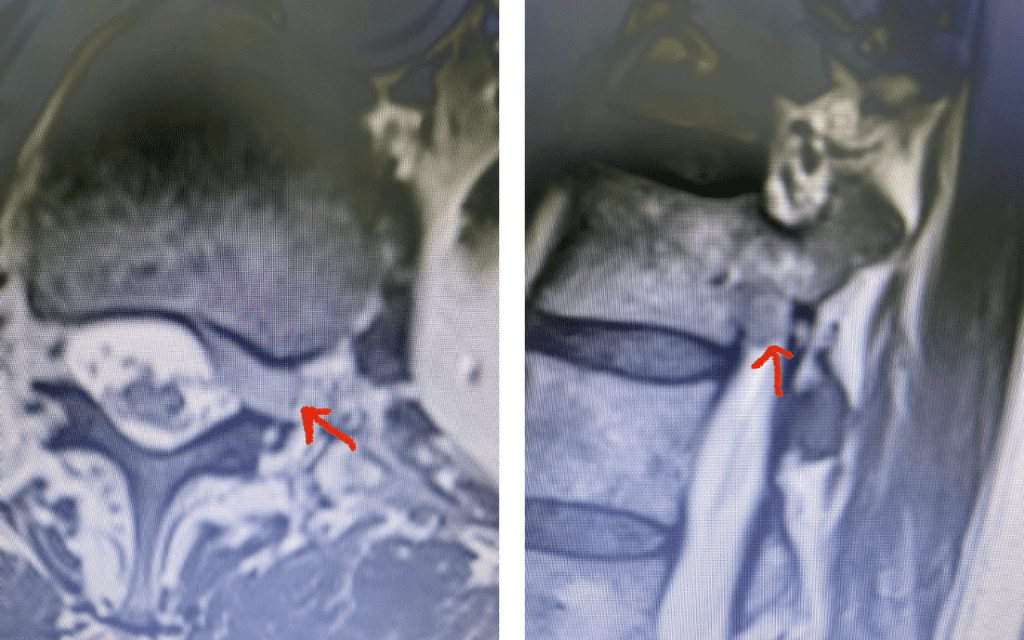

Fig 4: Axial and Sagittal T2-weighted lumbar MRI demonstrating a left lateral foraminal disc herniation (red arrow) causing compression of the exiting L1 nerve root against the undersurface of the pedicle of L1.

Fig 7: Sagittal T2-weighted lumbar MRI with side by side comparison of the normal open right L3-4 foramen (red arrow) compared to the left L3-4 foramen filled with a large disc fragment (red arrow).